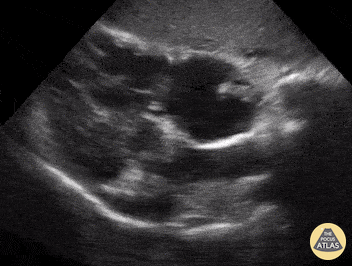

Right Ventricular Dysfunction - Clot in Transit

An 50-year-old presented with shortness of breath and suffered witnessed PEA arrest subsequent to having obtained this POCUS image (subcostal view) notable for a hyperechoic, mobile structure within the RA). ACLS was administered in addition to TPA and ROSC was achieved. Subsequent formal ultrasound, following thrombolytic administration, revealed absence of thrombus. Ryan Shelby PGY-3 EM Resident; @RyanShelby18 Central Michigan University